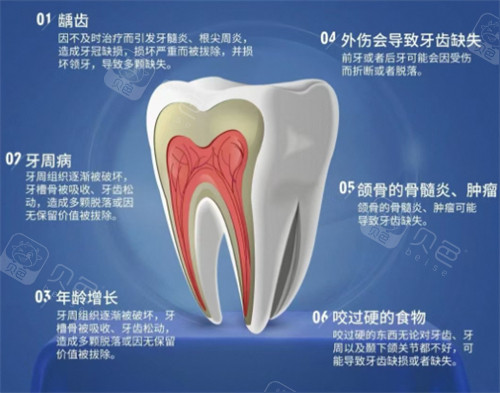

患者体验中,“服务温度”是洁仕博口腔的标签。一位接受隐形矫正的患者分享:“护士准备了咖啡和靠垫,治疗间隙还教我使用牙缝刷,细节很贴心。”此外,机构提供免费口腔检查,帮助患者早期发现龋齿、牙周病等问题,预防性服务理念深受好评。